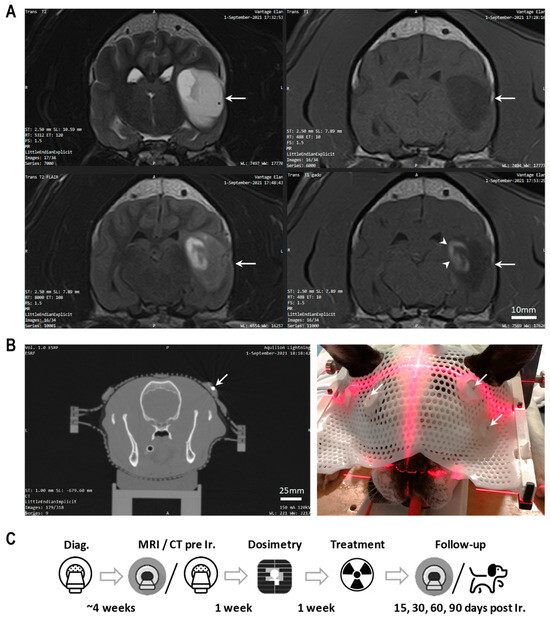

2.2. Treatment Planning, Dosimetry and Microbeam Radiation Therapy

2.3. Clinical Follow-Up after MRT

2.4. MR Imaging before and after MRT

3. Results